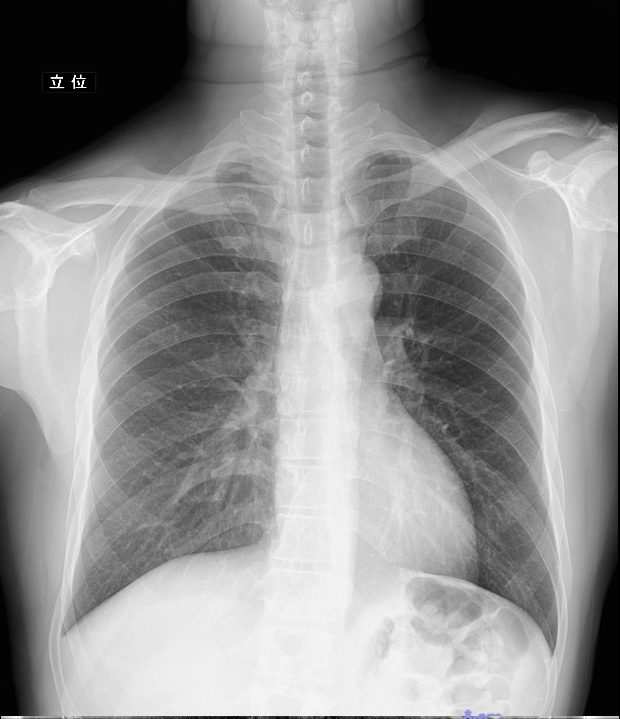

X線撮影装置

■Fujifilm社製 X線撮影装置(BENEO-Fx)

・FPD(フラットパネルディテクタ)による時間短縮

FPDとは、体を透過したX線を受け取りデジタル変換することでX線画像を得る装置です。画像を瞬時に確認できるため、従来の装置に比べ患者さんの検査時間、待ち時間が短縮されます。

・高画質で低被爆

また、FPDの特徴として少ないX線でも、高画質の画像が得られます。特に整形領域の骨の鮮明度が向上しました。

エネルギーサブトラクション

1度の胸部X線撮影で、エネルギーの異なるX線を照射し、そのエネルギー差で生じる2種類の画像(胸部画像①と骨画像②)を取得します。

①から②の画像を引き算(エネルギーサブトラクション)する事により、従来の胸部X線では妨げになっていた肋骨の陰影を消去し、小さな病変も見つけやすくなっています。

【①胸部画像】

【②骨画像】

【③軟部画像(①通常の胸部X線画像-②骨画像)】